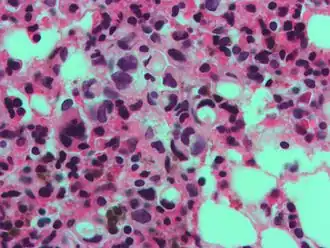

Een zegelringachtige opgeblazen macrofaag, die een kankercel kan nabootsen, maar de textuur van de kern is vergelijkbaar met die van een normale macrofaag. -

De naam van de cel komt door zijn uiterlijk; zegelringcellen lijken op een zegelring. Ze bevatten een grote hoeveelheid mucine, die de celkern naar de celperiferie duwt. De plas mucine in een zegelringcel bootst het uiterlijk na van een gat waar een vinger doorheen kan en de kern bootst het uiterlijk van de voorkant van de ring in profiel na.